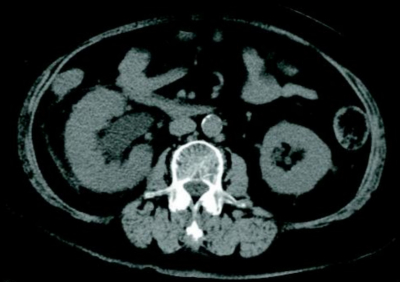

尿所見:蛋白1+、糖(-)、ケトン体(-)、潜血1+、沈渣は赤血球 10〜50/HPF、白血球 50〜99/HPF。血液所見:赤血球 434 万、Hb 11.8 g/dL、Ht 37 %、白血球2,200、血小板 22 万。血液生化学所見:総蛋白 6.5 g/dL、アルブミン 2.8 g/dL、AST 19 U/L、ALT 19 U/L、尿素窒素 12 mg/dL、クレアチニン 0.8 mg/dL。CRP 21 mg/dL。血液培養と尿培養の検体を採取し、生理食塩液による輸液を行ったが、血圧低下の改善はみられず、カテコラミンと抗菌薬の投与を開始した。腹部 CTを別に示す。